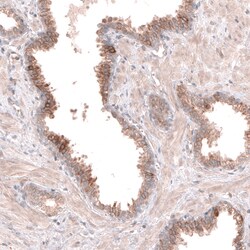

Invitrogen™ ACSL3 Polyclonal Antibody

Brand: Invitrogen™ PA582427

| Immunohistochemistry (Paraffin), Western Blot | |